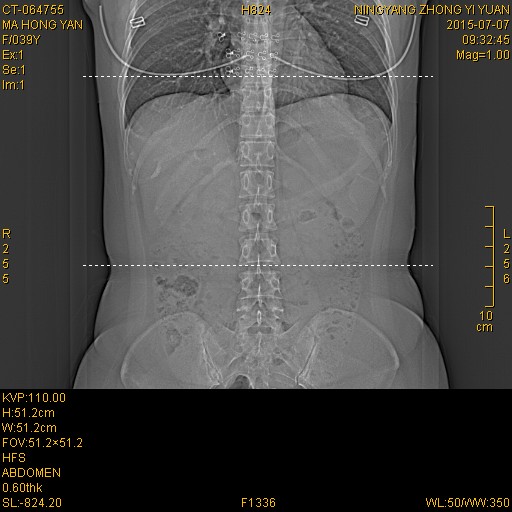

CT50808:腹部病变

女。39y 夜间腹部不适,漓芯;两次CT检查图像前后相差10天

前后两次高密度影及胆囊变化,不知怎么解释?请教

胆囊炎,胆囊结石